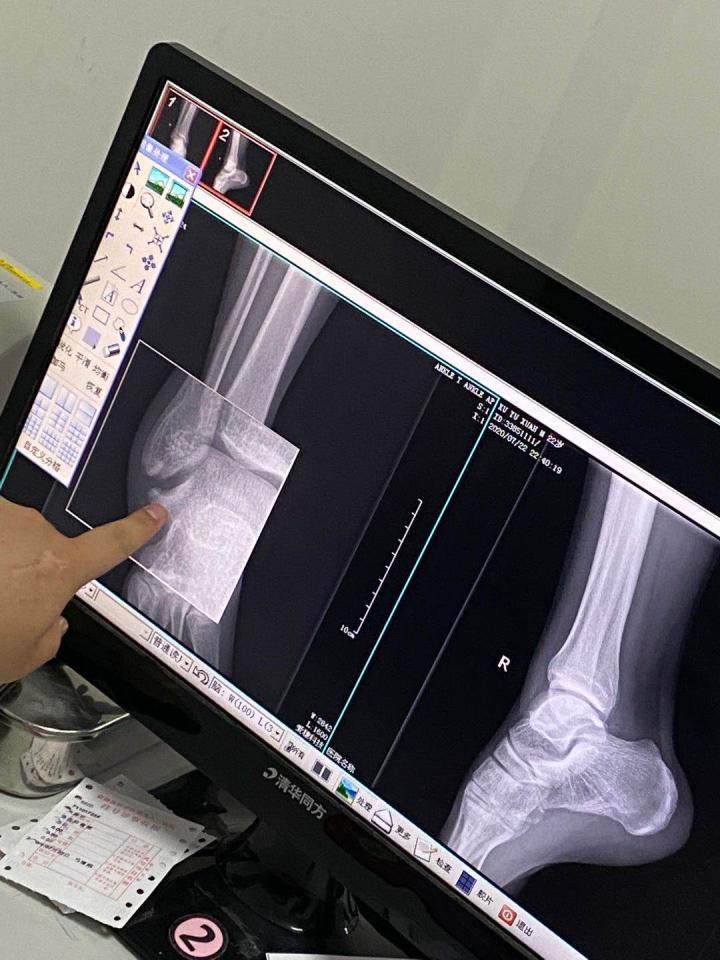

脚踝扭伤撕脱性骨折4周下地走路简单分享下康复过程以及错误治疗